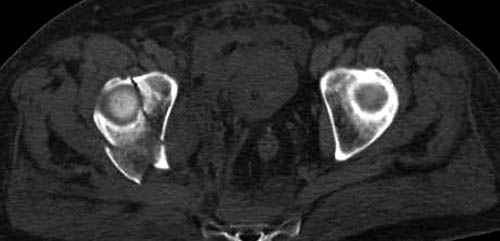

Дополнительно имеется перелом ацетабулума: задняя

колонна с полупоперечным переломом, и переломы костей лица.

На седьмой день зафиксирован перелом ацетабулума через задний доступ. Перед операцией для профилактики DVT, IVC фильтер, также получает Lovenox.

Извиняюсь за качества снимков, обычный больной в 300 фунтов, портативным ренген аппаратом не пробить.